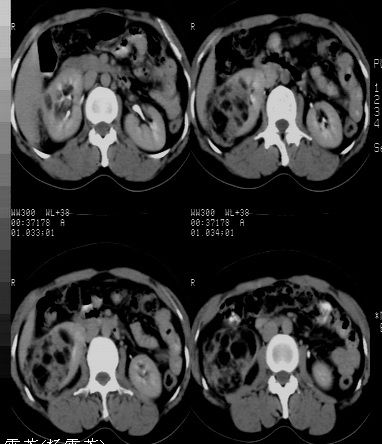

标题: CT24780:女 41岁 右肾多发低密度占位性病灶 [打印本页]

标题: CT24780:女 41岁 右肾多发低密度

女 41岁 超声检查:右肾多发实质性包块,性质待查(提示:错构瘤或其它病变),临床病史不详。